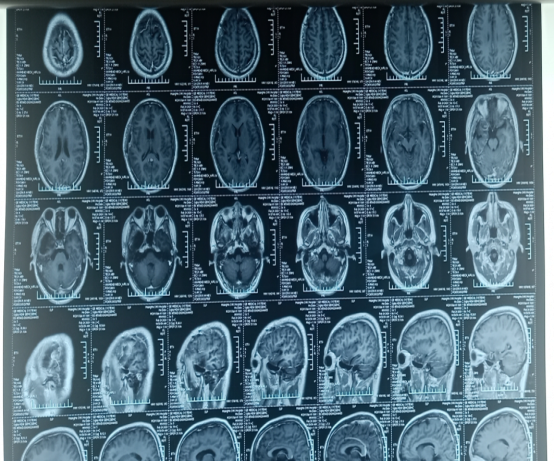

20190927郑州金水医院

20190927郑大一附院:右侧颞叶巨大占位,考虑胶质瘤。

术后MRI:20191005郑大一附院:“右颞部占位切除术”后改变。

放化疗后MRI:20191020西安交大